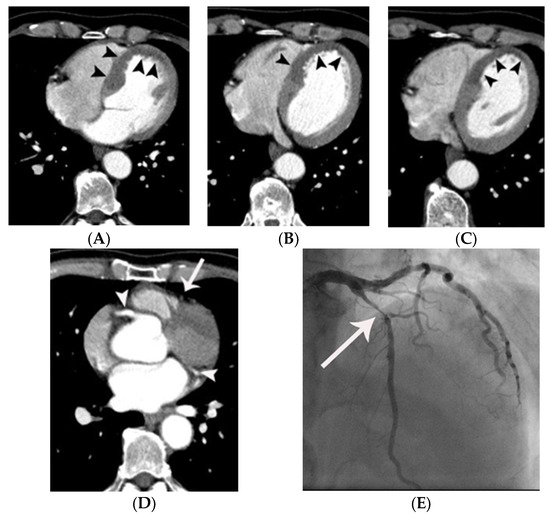

Figure 2.

Coronary artery occlusion in the mid-right coronary artery demonstrated on non-gated enhanced chest CT in a 67-year-old woman with acute myocardial infarction. (A) Artifact vs. true myocardial perfusion defect (arrowheads) was noted in the inferior wall of the left ventricle on an axial image. Suspicion of acute myocardial infarction was not described in the initial radiologic report. (B) On retrospective analysis of the coronary arteries, an abrupt cut-off (arrow) of contrast was noted in the mid-right coronary artery on a coronal reformatted image. Note that only minimal motion artifact is present in this image, even though the image was obtained without ECG gating. (C) Subsequent emergent coronary angiography confirmed the non-gated chest CT finding (arrowheads).

There were significant differences in the prevalence of normal, probable artifact or equivocal MPD, and probable MPD between the two groups (Table 2). There were 18.2% (6/33) and 0% (0/66) of patients showing CAO on non-gated chest CT in groups 1 and 2, respectively (p = 0.001). The location of the culprit lesion in the coronary arteries was variable in group 1 (Table 3) (Figure 2 and Figure 3).